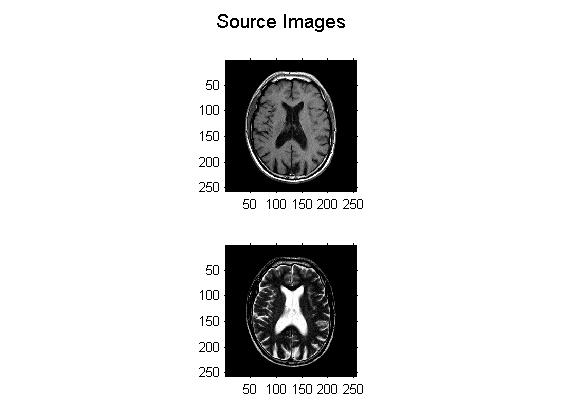

% Show source input images

figure;

no_of_images = size(I,4);

for i = 1:no_of_images

subplot(2,1,i); imshow(I(:,:,:,i));

end

suptitle('Source Images');